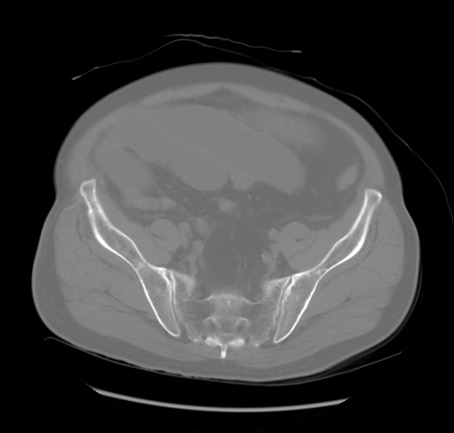

症例20(横断像)

【症例】 60歳代男性

【主訴】 腹部膨満、嘔吐

【現病歴】5日前頃より倦怠感を認め食事量減少し4日前の朝嘔吐、食事摂取困難となった。 3日前近医受診し点滴施行され整腸剤などを処方された。 当日他院を受診し、腹部膨満著明、炎症反応の上昇(CRP10.8、WBC11200)あり、紹介受診となる。

【身体所見】 意識JCS1 受け答えがはっきりしないBP 111/57mHg、 P 67bpm、、BT35.2°C、SpO2 97%(RA)、 腹部:膨隆、打診で鼓音あり、全体的に圧痛有り、腸蠕動音(-)、反跳痛ははっきりせず。

【データ】WBC 11400、CRP 14.20